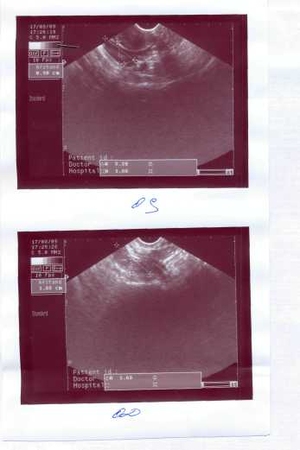

Съездила я вчера на УЗИ. Я такая счастливая и окрыленная.

Доменантный фолликул есть и как раз с левой стороны. Сказали, что О будет вот вот и нам уже надо приступать к стараниям. Узистка жестко сказала: жду с задержкой для определения срока Б с начале сентября. Только вот спаек я не избежала после ВБ, хотя так старалась(. Но она меня уверила что они не страшные и всегда возникают после таких операций. Главное что спайки не затронули ничего важного.

ВБ- внематочная беременность. Прошло 4 цикла. Делают мониторинг фоллукула. Смотрят как они развиваются и естьли доменантный, и видно будет О или нет. Вообще мне сказали делать УЗИ на 10, 12, 14,16 день цикла. Но я ходила на 12ДЦ и там уже все было видно и продолжать сказали нет смысла. Дела УЗИ к ИНВИТРО Новомарьинская ул.3, но вообще их очень много по Москве.